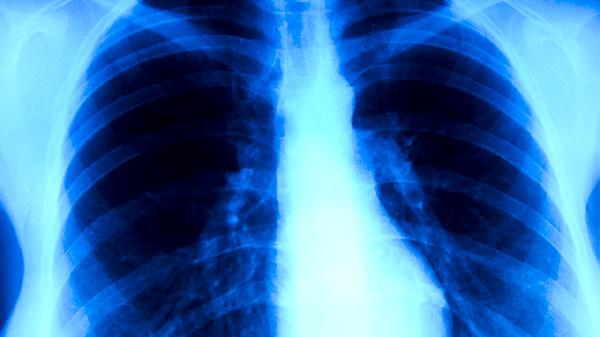

治療期間需每月復(fù)查胸部X線或CT,監(jiān)測病灶變化。每1-2周檢測血常規(guī)、肝腎功能,評估藥物安全性。痰涂片檢查需持續(xù)至連續(xù)3次陰性,確認(rèn)傳染性消失。若出現(xiàn)咯血、胸痛加重需立即復(fù)診。